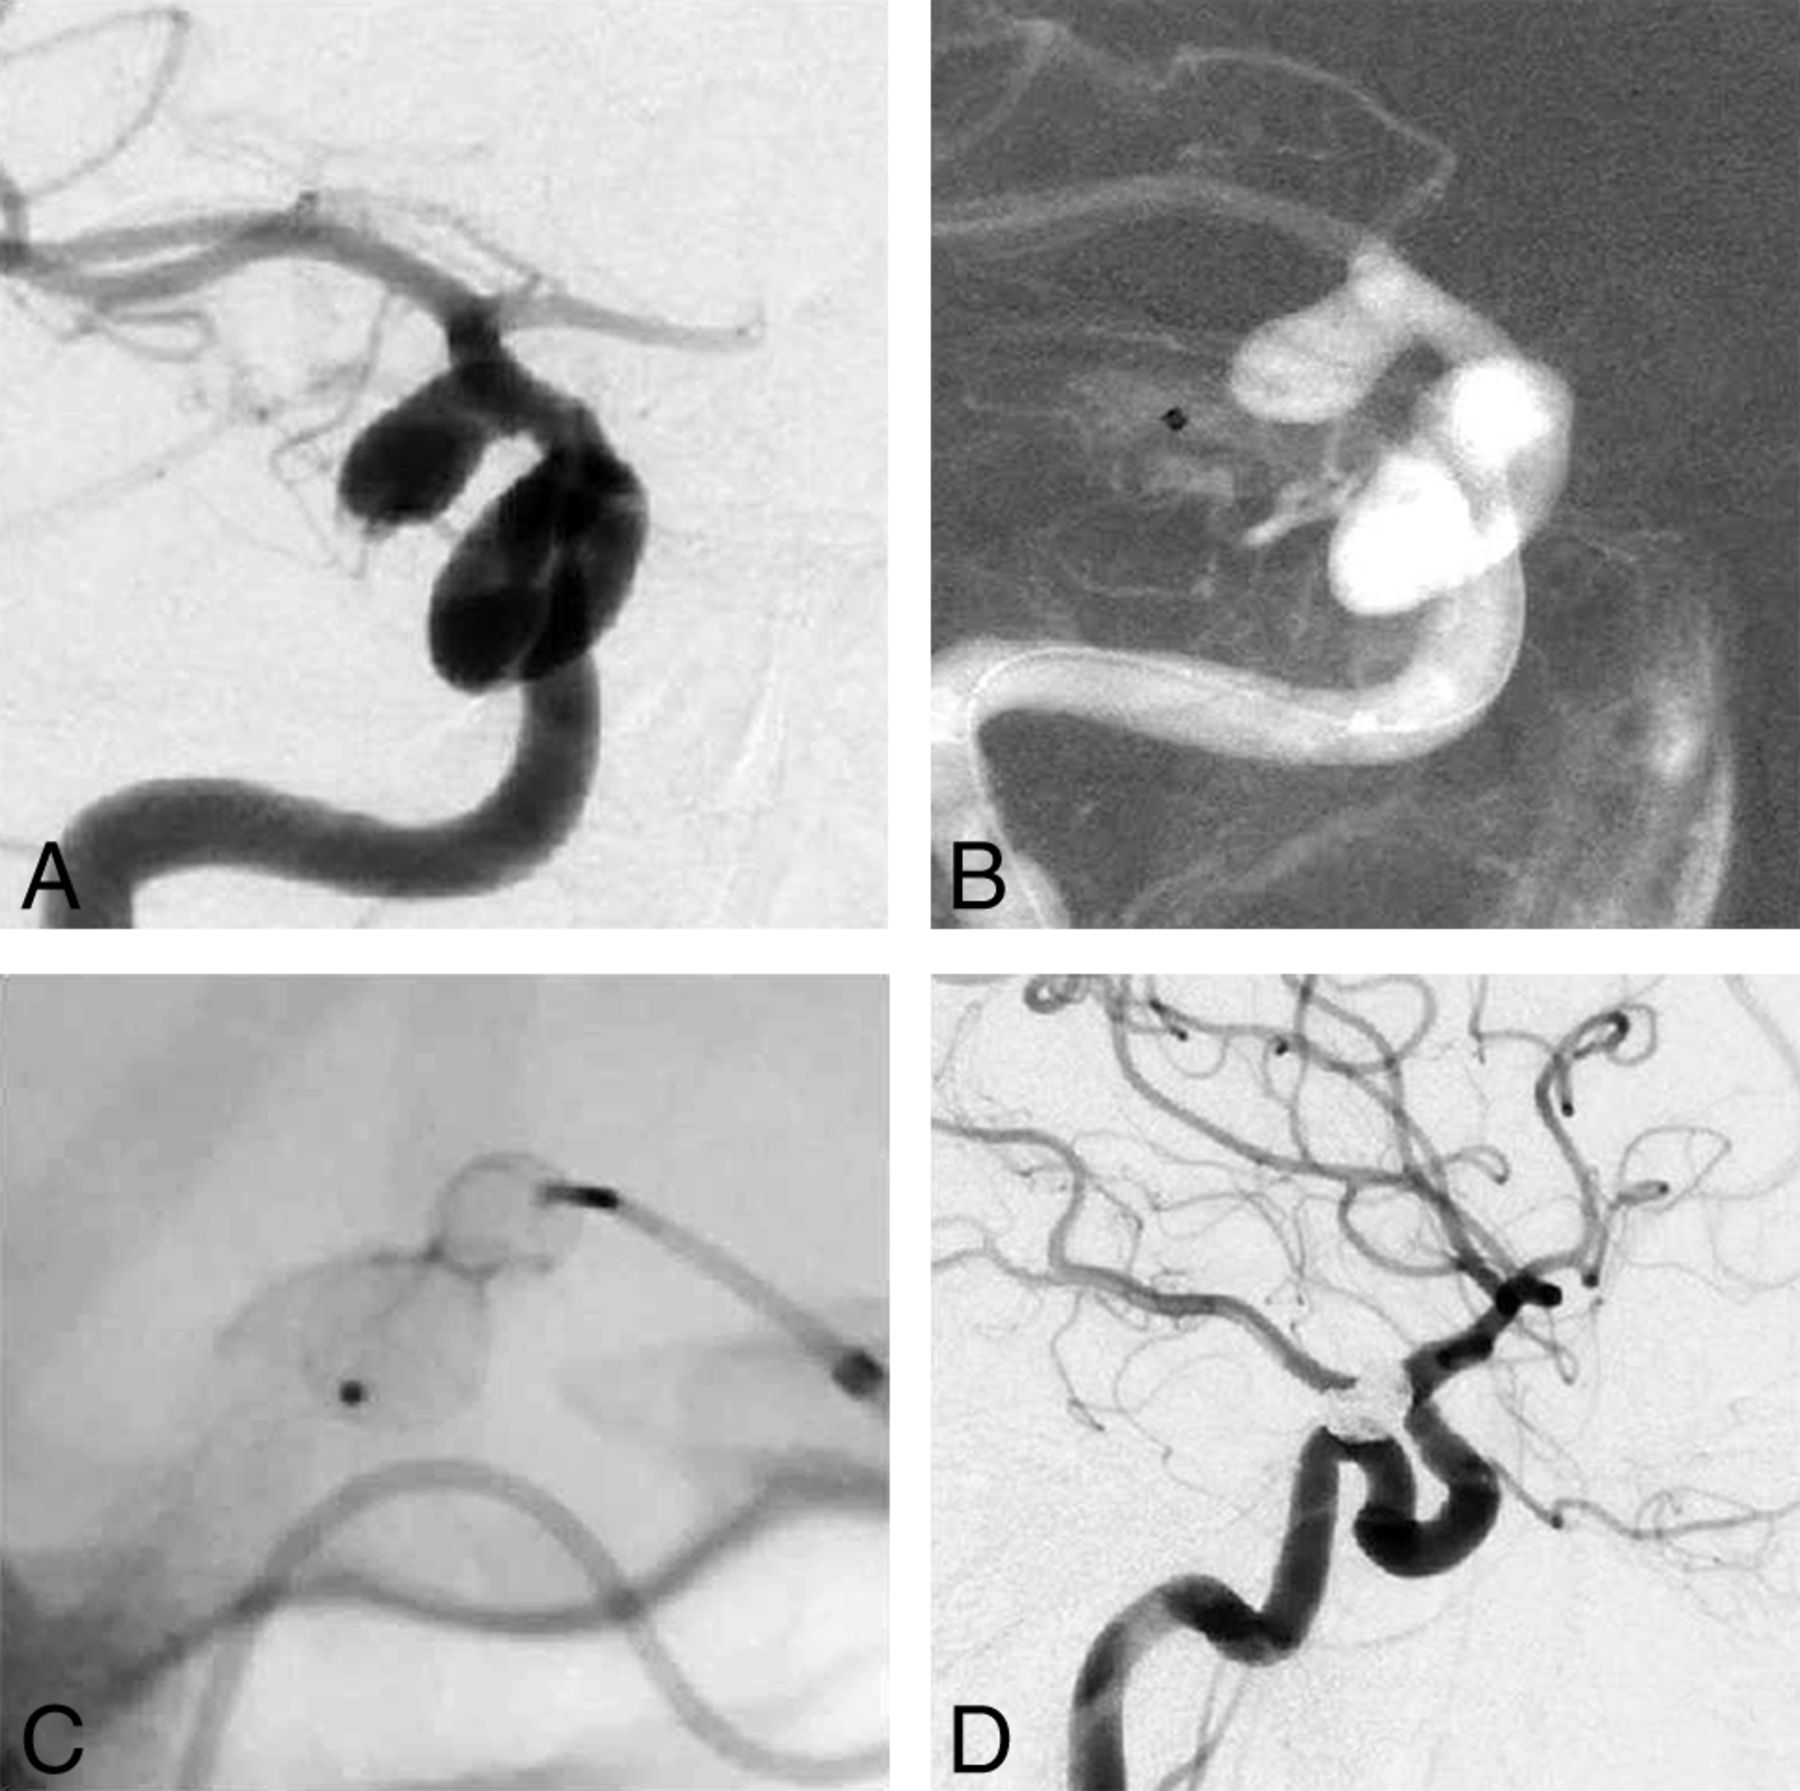

The procedure was completed with a WEB device only as intended in 83 (81.4%) aneurysms (Fig 1), whereas in 7 (6.9%), additional coils were necessary to completely fill the aneurysm. In another 8 (7.8%) procedures, a self-expanding stent was implanted to guarantee a stable position of the WEB. This was combined with additional coiling in 1 aneurysm.

A, Incidental finding of an aneurysm of the origin of the superior cerebellar artery (anteroposterior view). B, Implantation of a WEB SL 7–4 without flow disturbance in the parent arteries (anteroposterior view). C, Three-month follow-up angiography with complete occlusion of the aneurysm and reconstruction of the neck area (anteroposterior view).